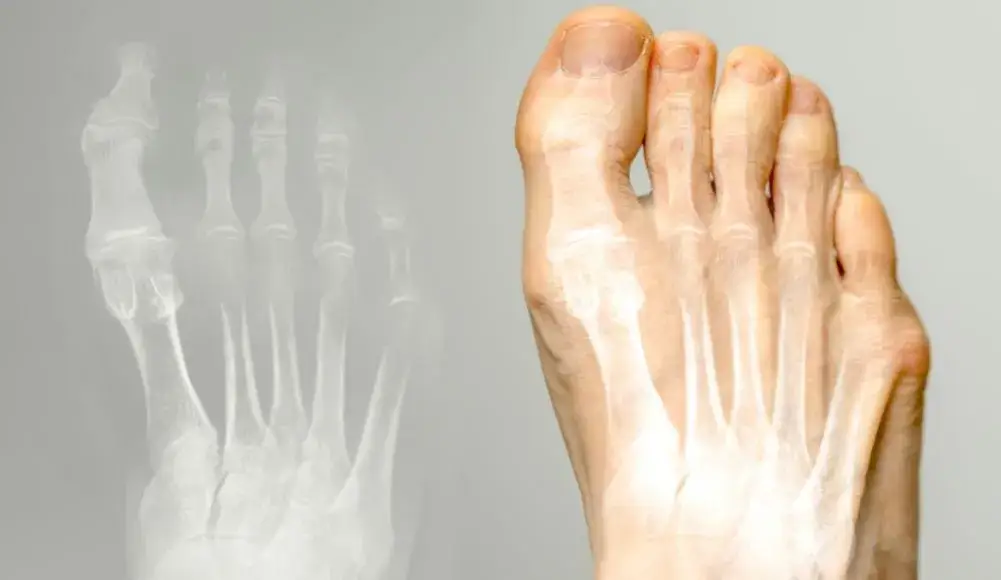

Haluks małego palca, określany w nomenklaturze medycznej jako deformacja Bunionette lub potocznie „kostka krawca”, to nic innego jak bolesne zniekształcenie w obrębie stawu śródstopno-paliczkowego piątego palca stopy. W przeciwieństwie do bardziej znanego haluksa (palucha koślawego), który dotyka dużego palca, Bunionette tworzy się po zewnętrznej krawędzi stopy, powodując charakterystyczne zgrubienie i często spory dyskomfort.

Wizyta u ortopedy staje się niezbędna, gdy leczenie zachowawcze nie przynosi oczekiwanych rezultatów, a objawy nasilają się. Sygnały alarmowe, które powinny skłonić Cię do pilnej konsultacji, to przede wszystkim brak poprawy po kilku tygodniach stosowania domowych metod i fizjoterapii, nasilający się ból, który utrudnia codzienne funkcjonowanie, znaczne pogorszenie deformacji oraz trudności w doborze obuwia, które stają się nie do zniesienia. Ortopeda dokładnie oceni stopień zaawansowania haluksa, zleci ewentualne badania obrazowe (np. RTG) i zaproponuje dalsze kroki leczenia, w tym rozważy opcję chirurgiczną.

Zabieg korekcji Bunionette ma na celu przywrócenie prawidłowej anatomii stopy i usunięcie bolesnego zgrubienia. Najczęściej wykonywaną procedurą jest osteotomia, czyli chirurgiczne przecięcie i przemieszczenie kości śródstopia w celu skorygowania jej osi i zmniejszenia wypukłości. Istnieją różne techniki osteotomii, które ortopeda dobiera indywidualnie do przypadku pacjenta. Zabiegi mogą być wykonywane metodami klasycznymi (z większym nacięciem) lub małoinwazyjnymi (przezskórnymi), które charakteryzują się mniejszymi nacięciami i szybszą rekonwalescencją, choć nie zawsze są możliwe do zastosowania.